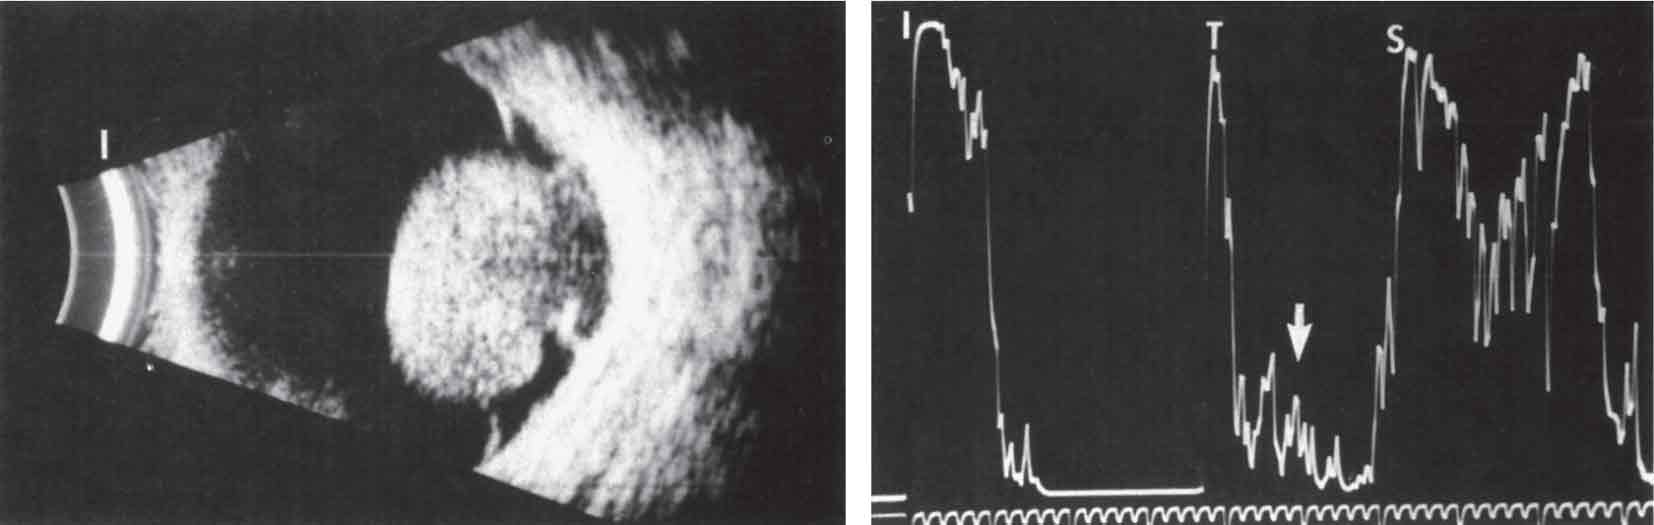

الشكل (16): التصوير المقطعي المحوسب في ورم أرومي شبكي ثنائي الجانب.

(لاحظ التكلسات ضمن الورم).

-(2 التصوير بالأمواج فوق الصوتية: يهدف إلى إظهار أبعاد الورم وموضعه، ووجود التكلس ضمنه.

- (3 التصوير المقطعي المحوسب: يساعد على كشف التكلسات داخل الورم (الشكل 16).